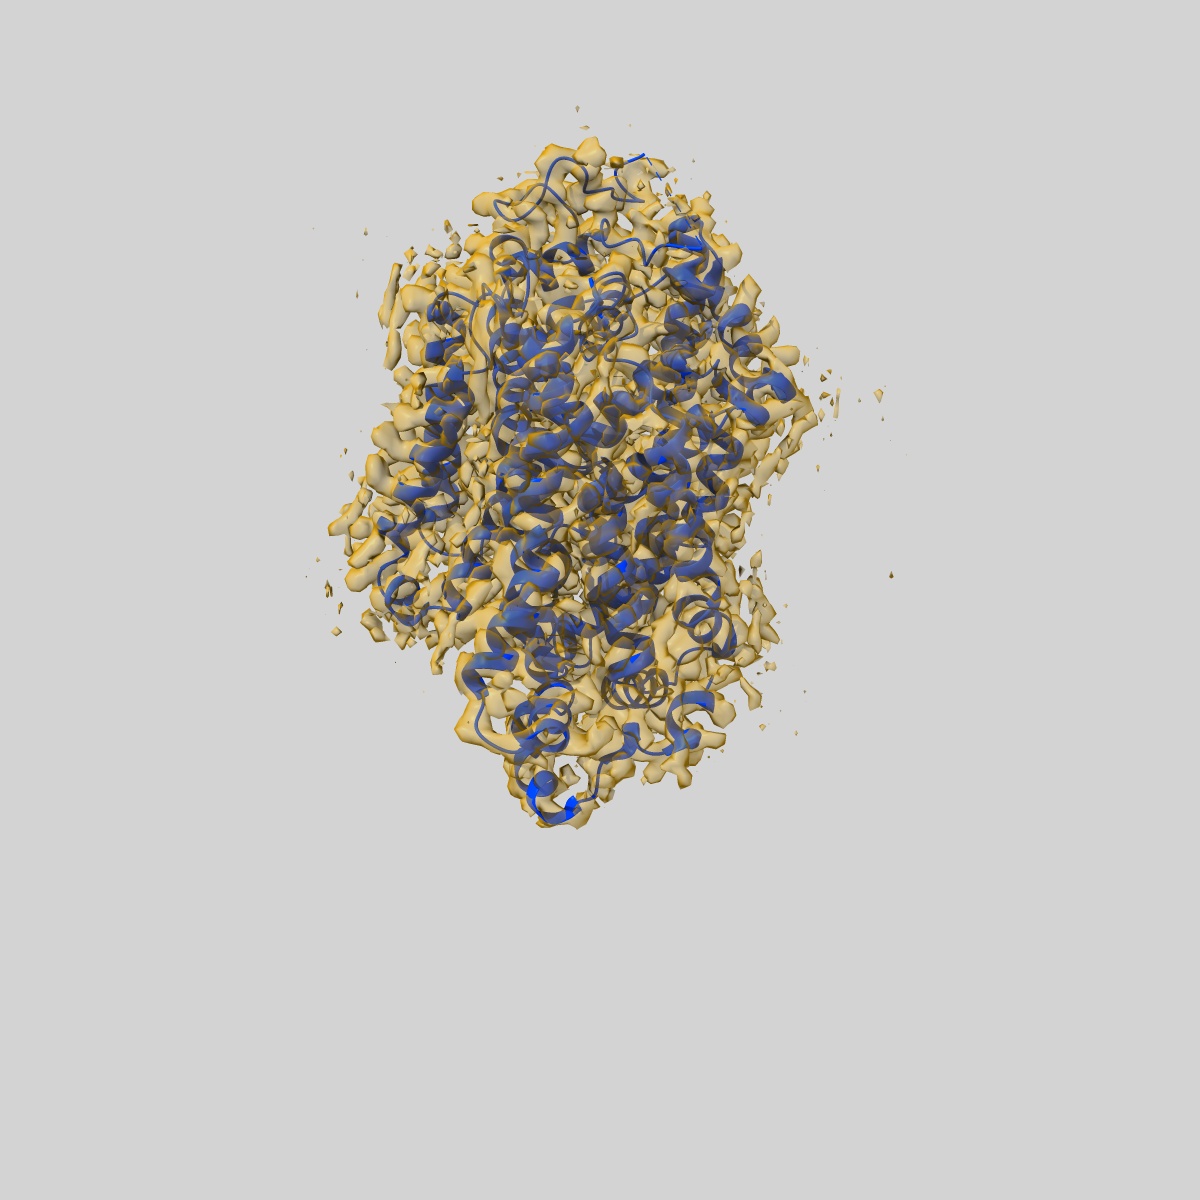

Cryo-EM structure of human norepinephrine transporter NET in the presence of the antidepressant desipramine in an inward-open state at resolution of 2.5 angstrom.

Single-particle2.5 Å

Fitted models: 8hfi

Molecular basis of human noradrenaline transporter reuptake and inhibition.

(2024) Nature , 632 , 921 - 929